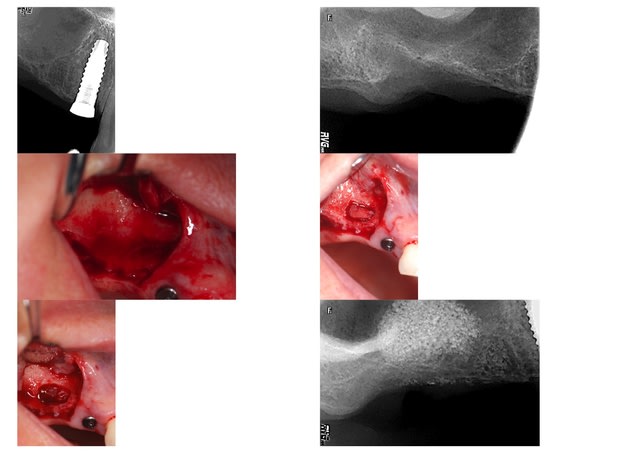

légende page 2 : 7/ fin du remplissage en 15; 8/ fin du remplissage en 17; 9/ avant pose de la membrane; 10/ après pose de la membrane

2ème utilisation du piezo pour un lift ce matin; toujours la même sensation de facilité et de sécurité; il est donc adopté définitivement pour le lift, ce qui n'est encore le cas pour les exo car il y pas mal de problème de cicatrisation dans cette utilisation, du fait très certainement de l'absence évidente de saignement post opératoire; pour en revenir au lift, la membrane était bien fine mais elle ne s'est pas déchirée; son décollement se fait très facilement et très rapidement avec les inserts; ce qui est donc perdu en temps à la découpe du volet est récupéré sans problème lors du décollement; l'implant n'a pas été posé simultanément car l'épaisseur de la crête au scanner était trop faible à mon goût (2 mm)